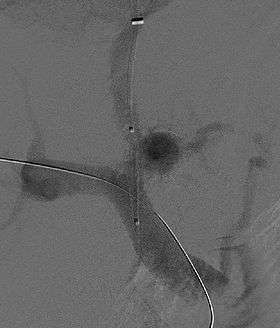

![]() Fluoroscopic image of TIPS in progress. A catheter has been passed into the hepatic vein and after needle puncture, a guidewire was passed into a portal vein branch. The tract was dilated with a balloon, and contrast injected. A self-expandable metallic stent has yet to be placed over the wire. | |

Transjugular intrahepatic portosystemic shunts are typically placed by an interventional radiologist under fluoroscopic guidance.[2] Access to the liver is gained, as the name 'transjugular' suggests, via the internal jugular vein in the neck. Once access to the jugular vein is confirmed, a guidewire and introducer sheath are typically placed to facilitate the shunt's placement. This enables the interventional radiologist to gain access to the patient's hepatic vein by traveling from the superior vena cava into the inferior vena cava and finally the hepatic vein. Once the catheter is in the hepatic vein, a wedge pressure is obtained to calculate the pressure gradient in the liver. Following this, carbon dioxide is injected to locate the portal vein. Then, a special needle known as a Colapinto is advanced through the liver parenchyma to connect the hepatic vein to the large portal vein, near the center of the liver. The channel for the shunt is next created by inflating an angioplasty balloon within the liver along the tract created by the needle. The shunt is completed by placing a special mesh tube known as a stent or endograft to maintain the tract between the higher-pressure portal vein and the lower-pressure hepatic vein. After the procedure, fluoroscopic images are made to show placement. Pressure in the portal vein and inferior vena cava are often measured.